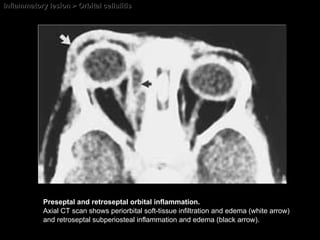

Inflammatory lesion > Orbital cellulitis Preseptal and retroseptal orbital inflammation.  Axial CT scan shows periorbital soft-tissue infiltration and edema (white arrow) and retroseptal subperiosteal inflammation and edema (black arrow).